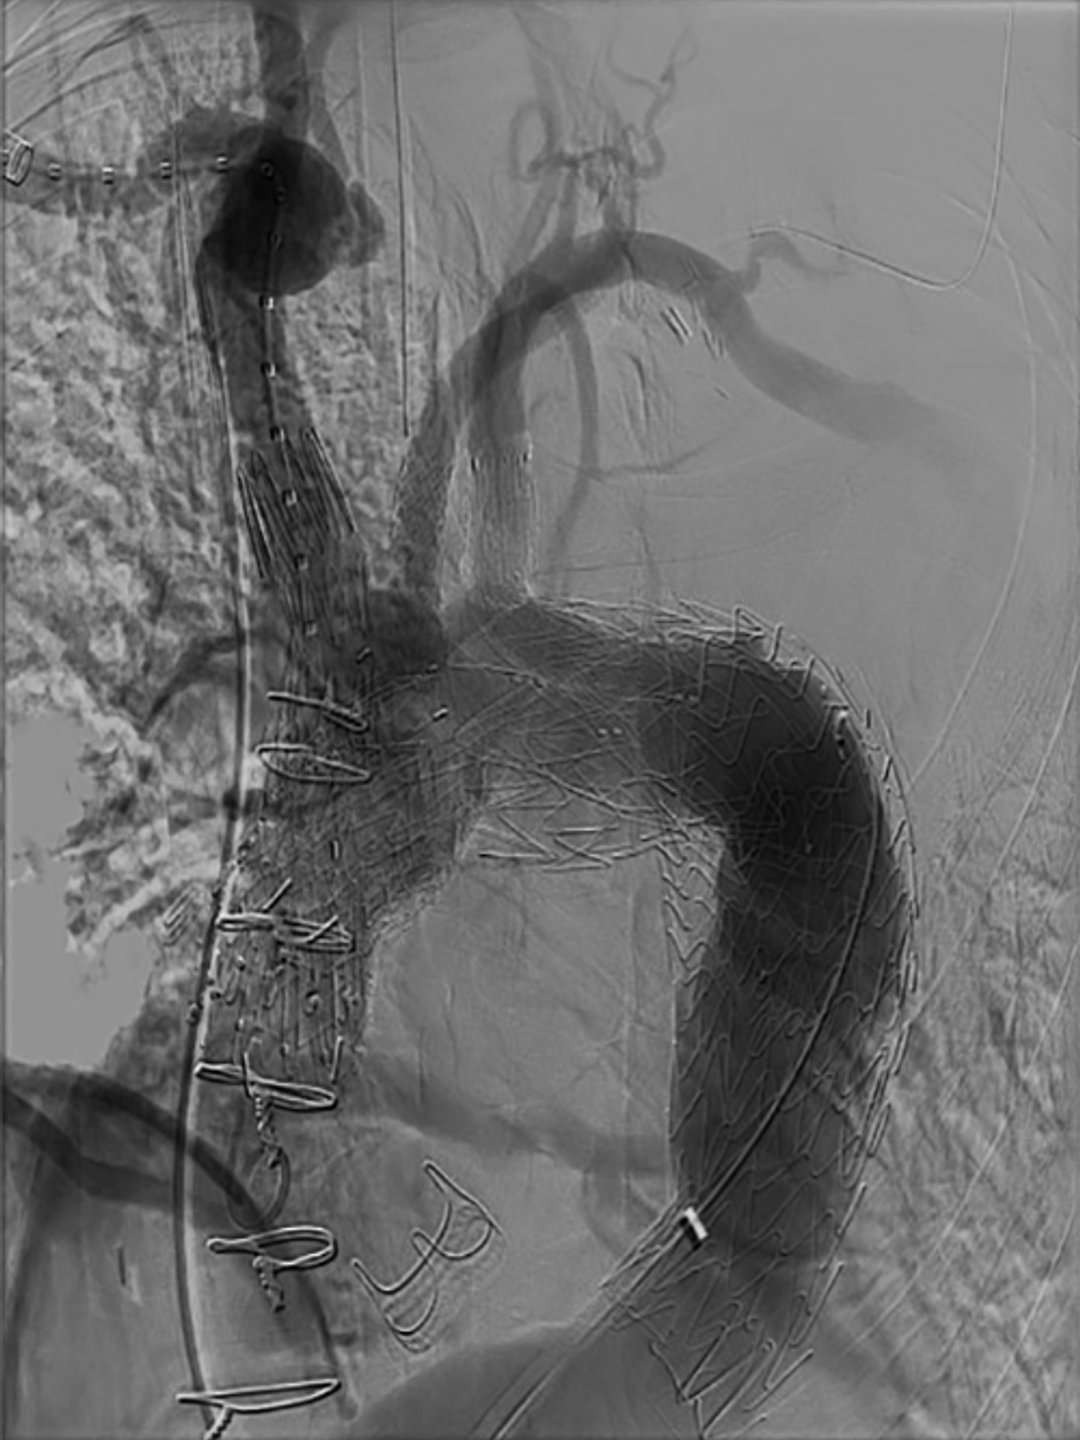

Total aortic arch repair involves the placement of branched and fenestrated stent grafts to reperfuse the aortic arch and each of its supra‐aortic branches

Total aortic arch repair involves the placement of branched and fenestrated stent grafts to reperfuse the aortic arch and each of its supra‐aortic branches.

A team of cardiac surgeons, endovascular specialists, and anesthesiologists at Penn Medicine recently completed a percutaneous 3-branch endovascular total arch repair for aortic aneurysm, an exceptionally complex achievement previously performed at only a handful of institutions in the world. The team included Drs. Darren Schneider, Nimesh Desai, Kendall Lawrence, and Jared Feinman.

The procedure was conducted using a custom device from Dr. Schneider's ongoing IDE clinical trial of endovascular repair for aortic arch and thoracoabdominal aortic aneurysms and represents a component of the thriving program of clinical practice and research in endovascular surgery at Penn Medicine.

"To our knowledge, this procedure was one of the first 10 to 15 entirely percutaneous endovascular aortic arch repairs done worldwide," Dr. Desai said, citing the team effort as a testament to strong collaboration among the departments and divisions of cardiac surgery and vascular surgery, anesthesia, neurology, OR nursing and radiology techs, inpatient and outpatient nurse practitioners, and the ICU staff.

Drs. Darren Scheneider and Nimesh Desai performing percutaneous total aortic arch repair at Penn Medicine

Drs. Darren Schneider and Nimesh Desai performing percutaneous total aortic arch repair at Penn Medicine.

Common elements in aortic arch repair include careful selection of patients on the basis of underlying pathology and patency of the AA and supra-aortic trunks; the application of individualized stents incorporating one to three branches and fenestrations to accommodate affected supra-aortic vessels; percutaneous device access and manipulation via the right proximal brachial and femoral arteries; continuous intraoperative imaging; continuous perfusion to avoid cerebral ischemia and embolization; as well as perfusion to the heart and distal organs.